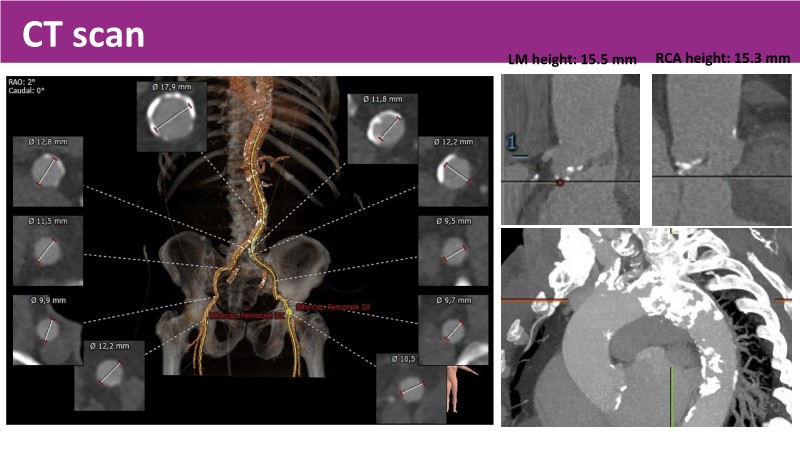

Discover the latest insights from the Myval THV series in this session from PCR London Valves 2025. Through real-world, case-based learning, the session explores lifetime management strategies for TAVI patients, the clinical relevance of intermediate and extra-large valve sizing, and the impact of foreshortening on accurate valve deployment.

Key presentations cover matching prostheses to patient anatomy, the importance of predictable valve performance in challenging situations, and pivotal trial data supporting Myval THV outcomes. Highlights include the OCTAPRO+ THV’s progressive design enabling precise deployment, the OctaAlign technique for commissural alignment, and next-generation strategies to optimize lifetime TAVI management.

- To appreciate the utility of intermediate and extra-large device sizing and the relationship between foreshortening and accurate deployment of THV